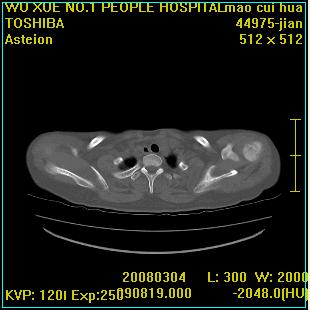

标题: CT12025:男,50岁,左肩活动受限半年。 [打印本页]

标题: CT12025:男,50岁,左肩活动受限半年。

肩关节骨质破坏呈小囊状,其周软组织轻度肿胀,余未见异常。

考虑:肩袖损伤。建议mri。

左侧肱骨头密度不均匀,高低混杂,周围软组织略肿胀,考虑结核性病变。

考虑左侧肱骨慢性骨髓炎。

左侧肱骨头密度不均匀,高低混杂,髓腔密度稍高,周围软组织略肿胀,肌间隙模糊,考虑慢性骨髓炎可能。密切结合临床!

肩关节周围软组织轻度肿胀,肌间隙模糊,余未见异常。

考虑:肩周炎。